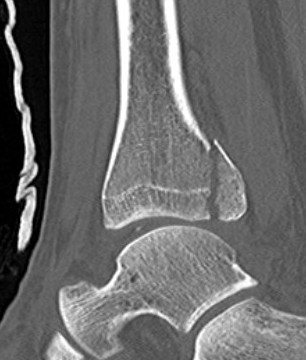

Mason and Malloy Classification

CT scan critical to classify and guide treatment / approach

| Type I | Type IIA | Type IIB | Type III |

|---|---|---|---|

| Avulsion of the PITFL |

Posterolateral fragment Volkmann fracture |

Posteromedial & posterolateral fragments Volkmann plus secondary fracture line |

Large coronal plane fragment Plafond fracture |